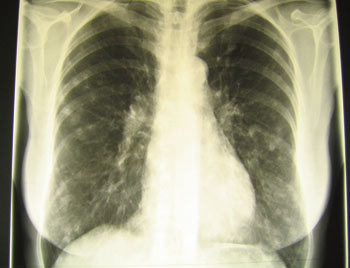

Røntgen thorax viste typiske forandringer med bilaterale nodulære infiltrater hos 13 av 15 pasienter (fig 3).

Påvisning av antistoff mot Histoplasma er den mest sensitive mikrobiologiske metoden for diagnostikk av akutt lungehistoplasmose (opptil 90 – 95 %), til sammenlikning med antigenpåvisning (25 – 75 %), mikroskopi (10 %) og dyrking av luftveissekret (15 %) (8). På røntgenbilde kan det ved akutt lungehistoplasmose påvises infiltrater, nodulære lesjoner og forstørrede lymfeknuter i lungehilus. Selv om dyrking er mindre sensitiv enn annen diagnostikk, bør dette likevel forsøkes, siden det gir det mest pålitelige svaret. Prøvene bør fortrinnsvis tas ved bronkoskopi, slik at man får materiale til dyrking fra nedre luftveier. Dersom dyrkingen er negativ, må diagnosen stilles ut fra en samlet vurdering av tilgjengelige opplysninger, dvs. anamnese, kliniske funn, røntgenfunn og serologi.